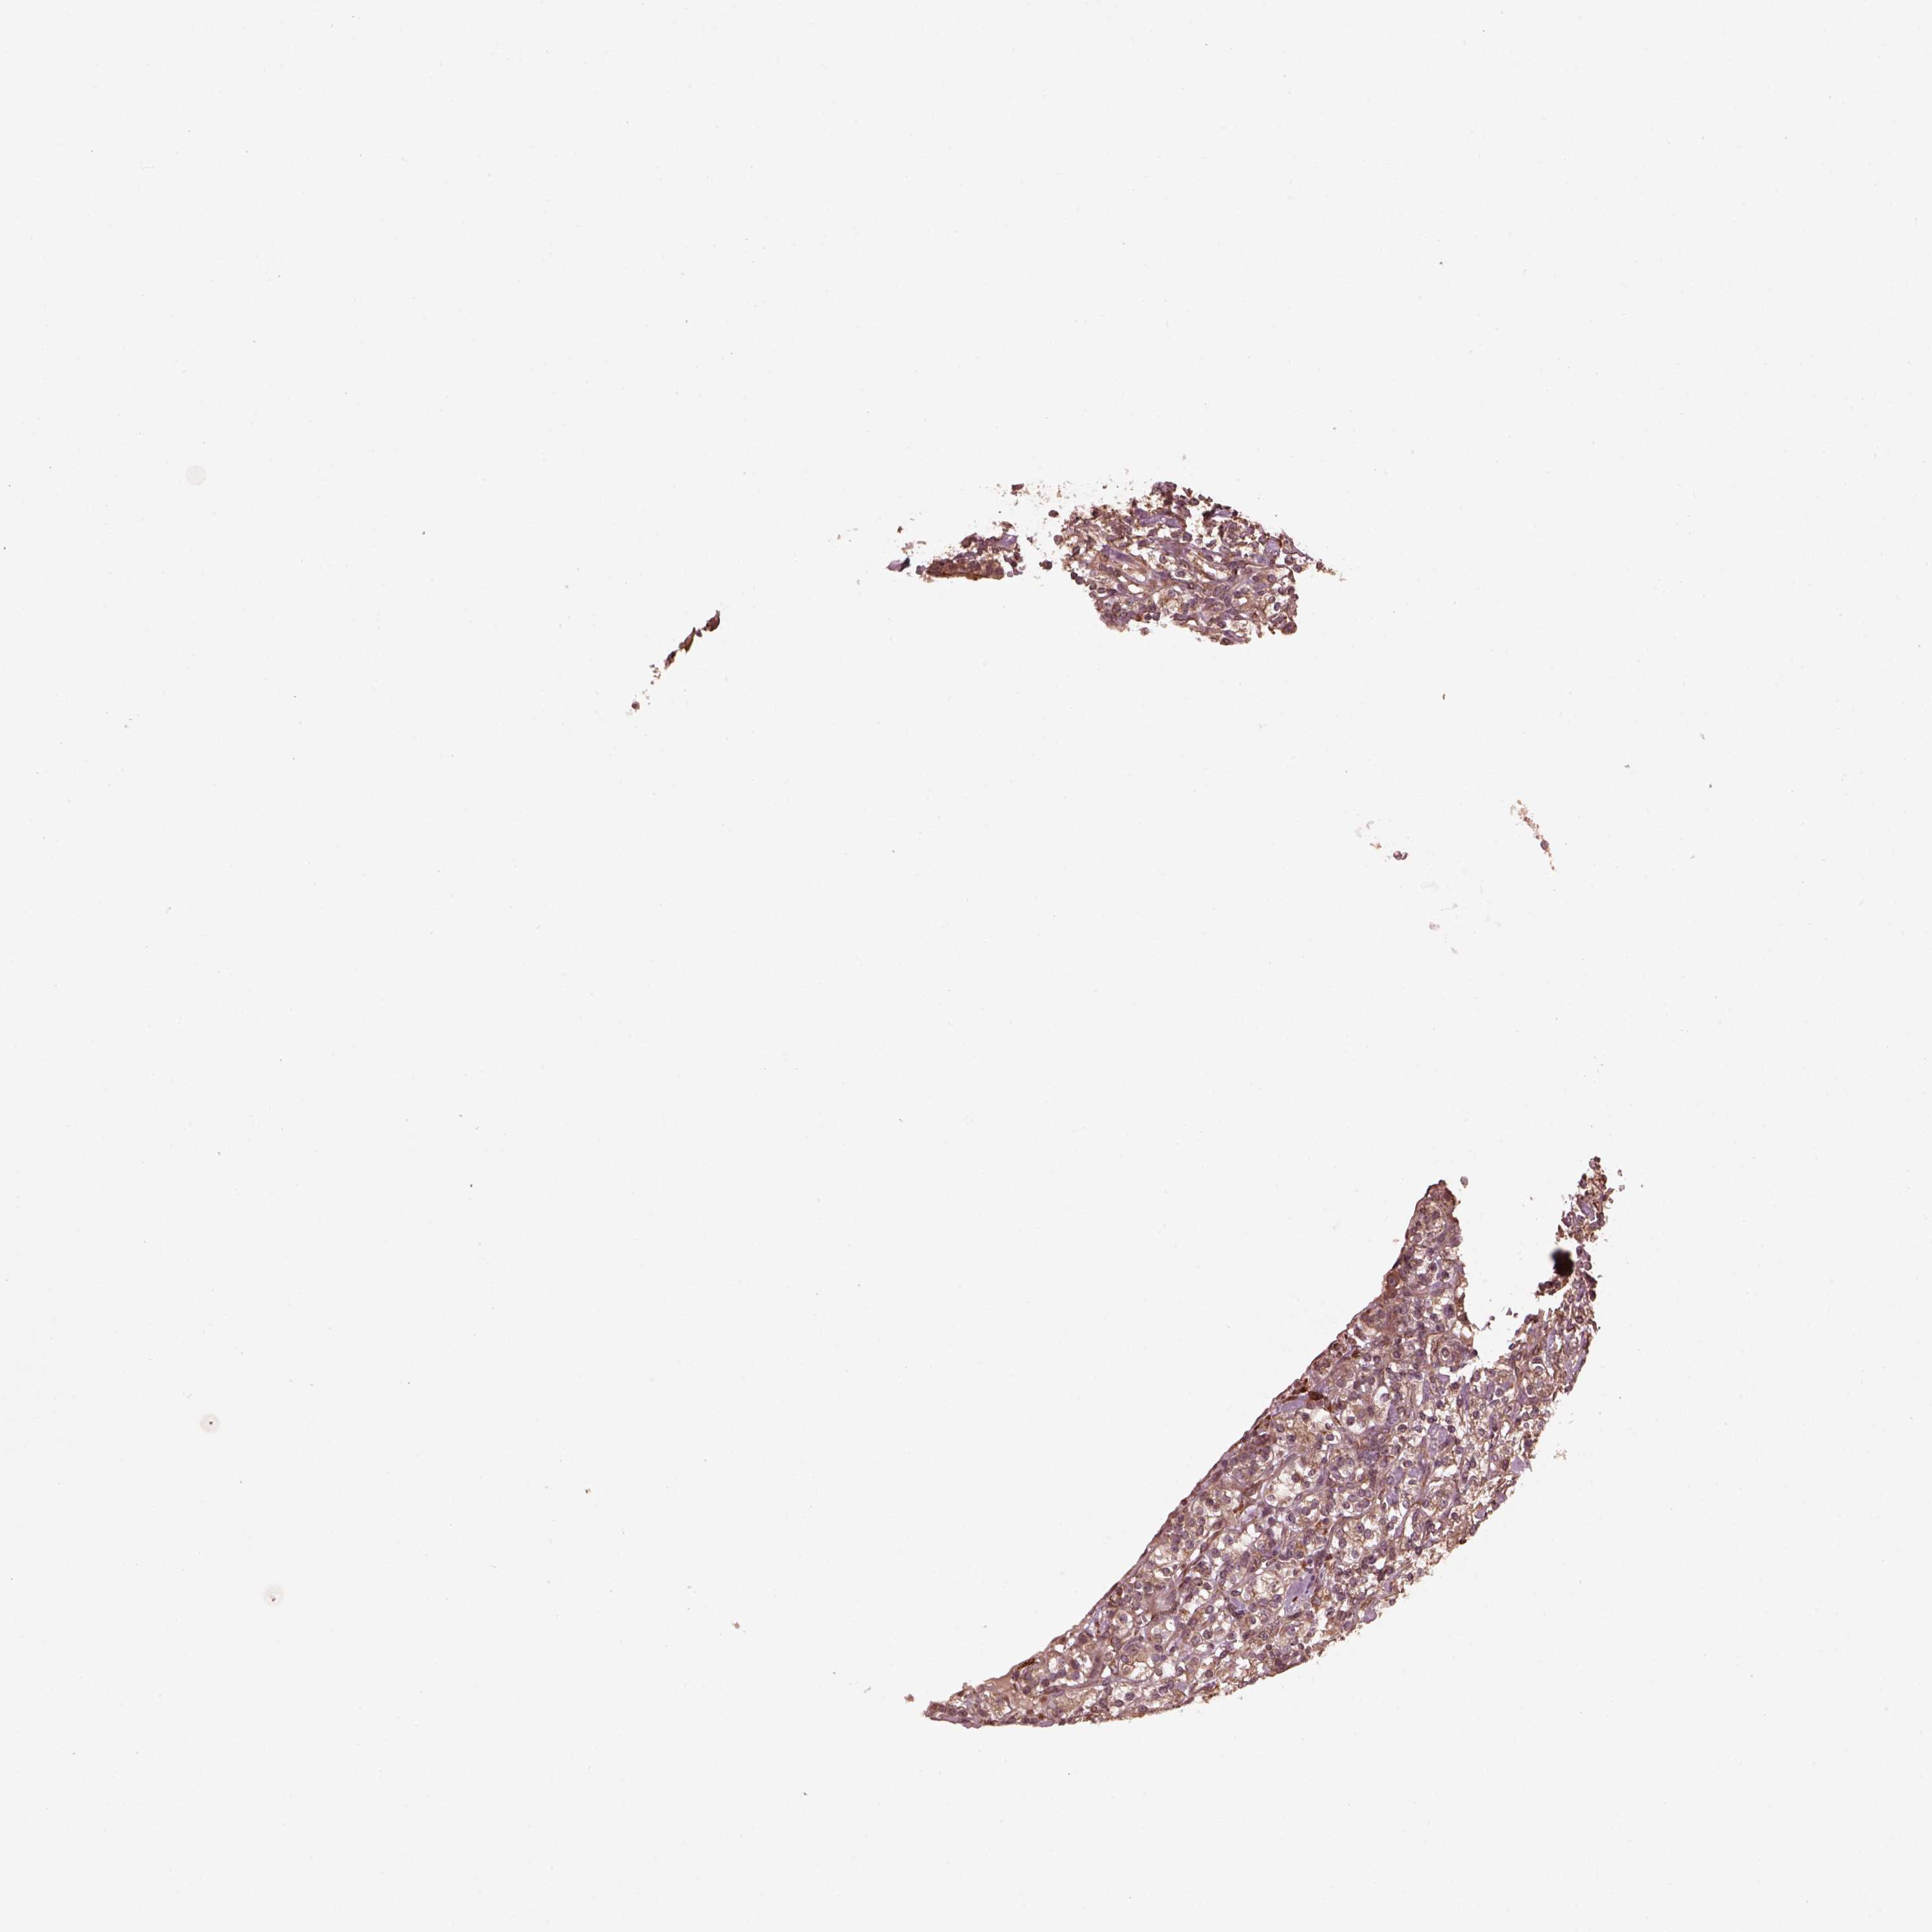

KIDNEY CHROMOPHOBE (TCGA) - Interactive survival scatter ploti

The Survival Scatter plot shows the clinical status (i.e. dead or alive) for all individuals in the patient cohort, based on the same data that underlies the corresponding Kaplan-Meier plots. Patients that are alive at last time for follow-up are shown in blue and patients who have died during the study are shown in red.

The x-axis shows the expression levels (FPKM) of the investigated gene in the tumor tissue at the time of diagnosis. The y-axis shows the follow-up time after diagnosis (years). Both axes are complimented with kernel density curves demonstrating the data density over the axes. The top density plot shows the expression levels (FPKM) distribution among dead (red) and alive patients (blue). The right density plot shows the data density of the survived years of dead patients with high and low expression levels respectively, stratified using the cutoff indicated by the vertical dashed line through the Survival Scatter plot. This cutoff is automatically defined based on the FPKM cutoff that minimizes the p-score. The cutoff can be changed by dragging the vertical line or by entering a cutoff value in the square labeled "Current cut-off".

Under the Survival Scatter plot the p-score landscape (black curve; left axis) is shown together with dead median separation (red curve; right axis). Dead median separation is the difference in median mRNA expression between patients who have died with high and low expression, respectively. It is calculated as follows: median FPKM expression of dead patients with high expression - median FPKM expression of dead patients with low expression. This is intended to aid the user in visually exploring custom cutoffs and the associated p-scores and dead median separation.

Individual patient data is displayed and can be filtered by clicking on one or more of the category buttons on the top of the page. Categories describing expression level and patient information include: high, low, alive, dead, female, male and tumor stages. The scale of the x-axis can be toggled between linear and log-scale by clicking on the "x log" button. Mouse-over function shows TCGA ID, patient information and mRNA expression (FPKM) for each patient.

& Survival analysisi

Kaplan-Meier plots summarize results from analysis of correlation between mRNA expression level and patient survival. Patients were divided based on level of expression into one of the two groups "low" (under cut off) or "high" (over cut off). X-axis shows time for survival (years) and y-axis shows the probability of survival, where 1.0 corresponds to 100 percent.

ZNF292 is not prognostic in Kidney Chromophobe (TCGA)

Best expression cut offi

Based on the FPKM value of each gene, patients were classified into two groups and association between prognosis (survival) and gene expression (FPKM) was examined. The best expression cut-off refers the FPKM value that yields maximal difference with regard to survival between the two groups at the lowest log-rank P-value. Best expression cut-off was selected based on survival analysis .

When clicking on this number, the vertical dashed line indicating cut-off, the interactive survival plot, and the Kaplan-Meier curve will be adjusted to show results based on the best expression cut-off.

: 16.95

TCGA RNA samplesi

RNA-seq data is reported as average FPKM (number Fragments Per Kilobase of exon per Million reads), generated by the The Cancer Genome Atlas (TCGA) .

Normal distribution across the dataset is visualized with box plots, shown as median and 25th and 75th percentiles. Points are displayed as outliers if they are above or below 1.5 times the interquartile range. FPKM values of the individual samples are presented next to the box plot.

Average pTPM 12.0

Number of samples 64